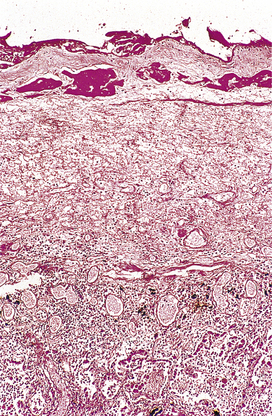

Microscopic features of chronic inflammation

The cellular infiltrate consists characteristically of lymphocytes, plasma cells and macrophages. A few eosinophil polymorphs may be present, but neutrophil polymorphs are scarce. Some of the macrophages may form multinucleate giant cells. Exudation of fluid is not a prominent feature, but there may be production of new fibrous tissue from granulation tissue (Figs 10.15-10.17). There may be evidence of continuing destruction of tissue at the same time as tissue regeneration and repair. Tissue necrosis may be a prominent feature, especially in granulomatous conditions such as tuberculosis. It is not usually possible to predict the causative factor from the histological appearances in chronic inflammation.

image

Fig. 10.17 Chronic inflammation in the wall of a gallbladder that has experienced previous episodes of acute cholecystitis. Aggregates of lymphocytes are appearing and there are ingrowing fibroblasts.